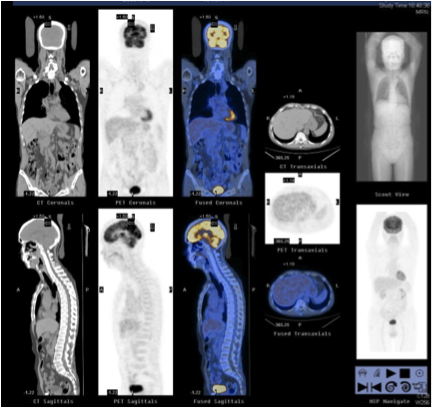

Three months later, patient was admitted for obstructive jaundice. His liver function was deranged with bilirubin 132, ALP 386, ALT 346. Ultrasound abdomen showed dilated common bile duct. Patient had the endoscopic retrograde cholangiopancreatography (ERCP) done and it found smooth stricture at common hepatic duct close to hila. Ampulla biopsy showed benign small bowel mucosa with focal neutrophilic intraepithelial infiltration and ulceration. There was no evidence of malignancy. Contrast CT abdomen and pelvis was also performed. It revealed again dilated common bile duct. Also there were multiple enlarged portal, mesenteric, retroperitoneal and groin lymph nodes. He had a 1cm cystic lesion at the tail of pancreas. In view of suspected malignancy, positron emission tomography (PET) was done (Fig 3A, 3B). There was no hypermetabolic lesion in liver and pancreas, but multiple hypermetebolic lymph nodes were found in head, neck, thorax, abdomen and pelvis. Also the bilateral submandibular glands showed intense FDG uptake with SUV max 7.5.

Patient was treated with prednisolone 30mg daily, and then had the prednisolone tailing down to 10mg daily with azathioprine 50mg daily added. The PET scan 3 months after treatment showed significant metabolic improvement (Fig 5). CT thorax also showed decreased tree-in-bud opacities and septal thickening.